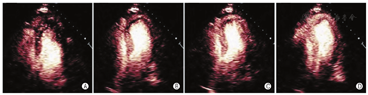

致密化不全心肌病是一种不常见但却逐渐被大家认识的疾病,会导致心力衰竭、心律失常、心脏栓塞事件及死亡。原因是心肌结构改变,表现为心肌节段性室壁运动减弱伴有两层结构的心肌肥厚:通常是一层致密化的薄的心外膜下的心肌及一层厚的不致密的心内膜下的心肌。当怀疑左室致密化不全但传统的二维成像无法充分显现时,非致密层特征性的深小梁间隐窝可通过左室小梁之间对比剂填充进行判断(图4)。在这种情况下,推荐应用谐波中等强度MI成像(如增至0.3~0.5)而非常规的低MI成像,从而可以更清晰地显示肌小梁的结构[1,38]。实时帧速下较高的机械指数可以在再灌注之前将肌小梁之间的低速微泡破坏,而保证左室腔内高速微泡的再灌注,从而更好地描记致密化不全层(图4)。

在进行心肌增强超声心动图灌注成像时,如评估再灌注治疗对心肌梗死的疗效或评估心肌存活情况,会出现"有或无"两种灌注情况。对于这些情况,我们只需要评估微血管是否完整[91,92]。在MCE中,通过团注和连续输注UEA已经可以进行心肌血流量和容量的定量评估。测量快速团注UEA后首过的技术,联合其他无创成像技术,已经应用于MCE[93]。然而,这种方法并不推荐用于MCE,因为难以做到:①在造影剂首次通过心脏时对整个心脏进行成像;②充分考虑到在造影剂从静脉转运至全身时的扩散与分布。为此,我们对MCE的灌注成像技术进行了改进,测量灌注成像的两个主要参数:①灌注活跃的微血管单位的实时数量(微血管血流量[MBV]),②通过这些微血管的血流速率[94],这些参数的测量依赖于超声能量可影响微泡完整性这种独特能力[94,95]。大于0.8的高机械指数可破坏微循环内的微泡,从而消除它们的增强信号。微泡再入微循环的局部时间强度分析可评估微泡再填充的速率和程度,这分别反映了微循环通过速率和心肌血流量(MBV)(图9)。这个方法推荐使用于:①通过连续注射来维持循环中稳定的微泡浓度;②仅使用几个高能量的"闪击"信号(避免影响循环的浓度);③仅分析心脏收缩末期图像帧(消除来自心肌内大血管的信号)[96,97]。写作组发现,小剂量单次注射UEA并进行缓慢盐水冲洗,在注射后的一段时间内微泡浓度符合稳态动力学,且在临床中已用于检测信号再填充和MBV[53,55]。去除本底影响的信号强度数据可以拟合成指数方程:Y=A[1-e(-βt)],其中y是闪击脉冲后任何时间t时的造影剂信号强度,A是造影剂到达平台期的信号强度,反映相对MBV,速率常数β(s-1)反映微泡通过微循环的速率[94]。血容量和血流速度的乘积(A·β)是心肌血流量的半定量指数,而绝对血流量可以通过将A值以血池信号标化得到绝对的MBV。